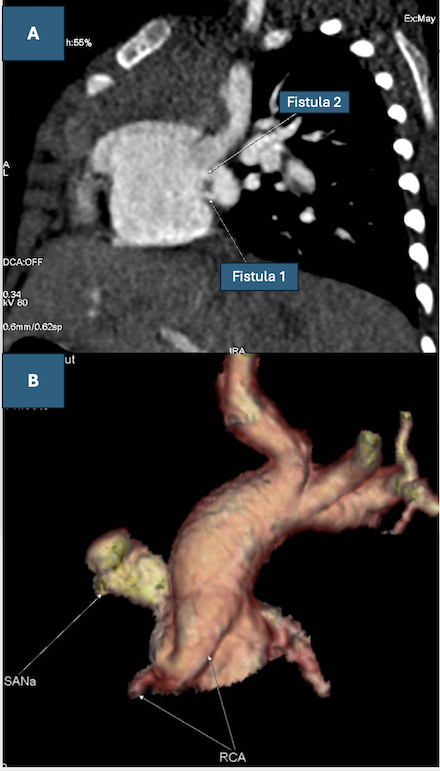

A 4-month-old female infant presented with cough and fever. A cardiac murmur was noted at the pulmonary valve area. Lab tests revealed mildly elevated WBC and CRP. CXR was unremarkable. TTE showed a markedly dilated RCA ostium (6.8 mm) and a saccular aneurysm arising from the proximal RCA communicating with the RA. Contrast-enhanced CCTA with 3D reconstruction confirmed an RCA ostial diameter of 5.5 mm, a 7 mm SNA aneurysm draining into the RA through two fistulas (2.0 mm and 2.5 mm). There were no clinical or laboratory findings suggestive of Kawasaki disease (KD). Surgical repair was performed with a right axillary thoracotomy approach. Proximal ligation of the sinoatrial nodal aneurysm (SNA) was performed, guided by an occlusion test. Postoperatively, P waves were absent on ECG on day 1 but reappeared by day 2. The postoperative course was uneventful.

This case presents the youngest reported patient with the rare triad of a RCA aneurysm, SNA aneurysm, and dual coronary artery fistulas (CAF) draining into the RA. Previous reports are limited and exclusively involve adults. CAF is rare, with a prevalence of 0.002% in the population. Multiple fistulas are 10.7% to 16% of these cases. This case does not align with KD, the most common cause of coronary artery aneurysms (CAA) in children. Given the localization of lesions to the RCA and SNA instead of diffused coronary dilation, a congenital abnormality is the most plausible etiology.